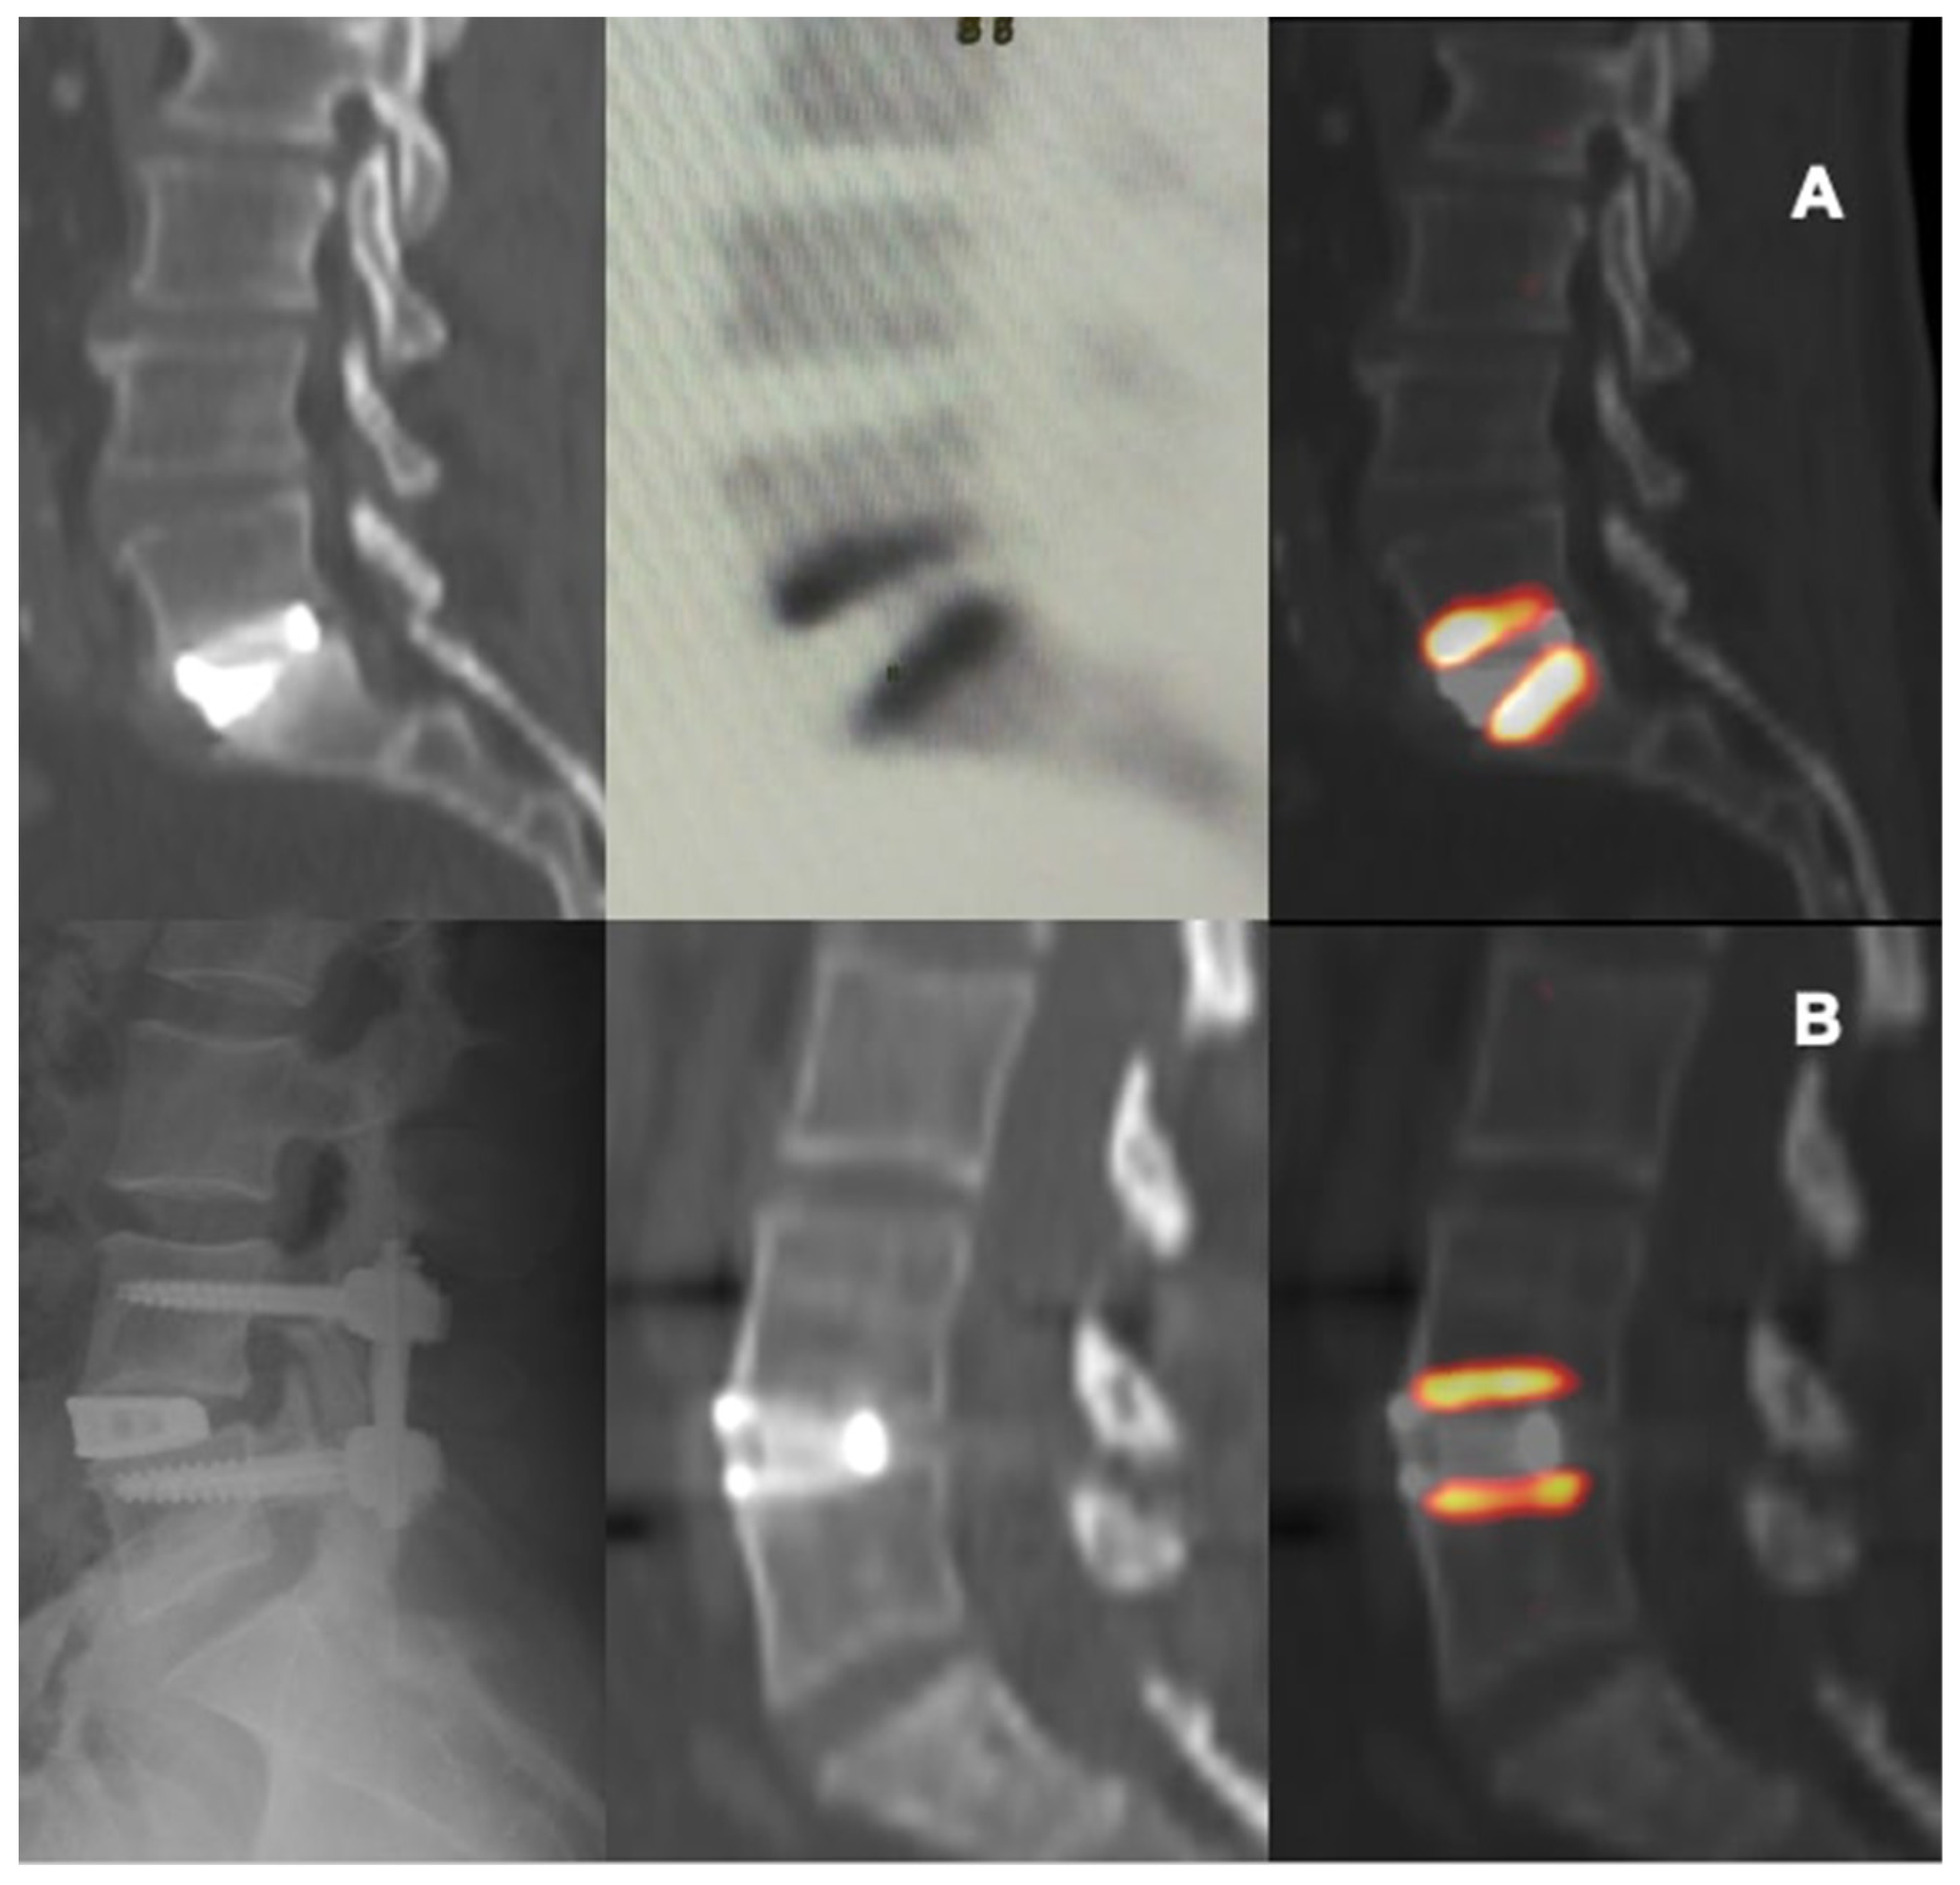

Figure 4.

CT and PET images showing metabolic activity on vertebral plates after arthrodesis surgery with trabecular titanium cage. L5-S1 ALIF, 11 weeks (A); L4-L5 XLIF, 27 weeks (B).

In this study the use of 18F-NaF PET/CT provided some adjunctive information about the metabolic-reparative reaction following the implantation of an interbody fusion cage during clinical follow-up; PET/CT supports the evidence regarding the ability of the cage to reach effective early osteo-integration.(Figure 4 and Figure 5) and provide some indications regarding the time required for the bone-remodeling process (the patients underwent PET examinations at different times and this has undoubtedly helped to give value to the final results).

According to our results, tracer uptake was already visible in the first week after implantation. This first finding is probably related to the increase in blood flow after preparation of the vertebral endplate and to the consequent bone-cell activation at the contact surface. Therefore the metabolic activity, probably linked to the osteogenic activity, increases progressively until reaching a peak between approximately the 3rd and 4th month after surgery (Figure 2 and Figure 3). This progressive increase in activity can be correlated, as supported by in vitro studies, to the migration, adhesion, and growth of cells from the vertebral bone tissue and to consequent osteoblastic activity with apposition of the bone matrix within the cage pores [34]. In the later stages, the metabolic hyperactivity on the vertebral endplates decreases progressively and tends to disappears around the 10th–12th month after surgery (Figure 2 and Figure 3). This reduction may be the expression of a lower need for bone remodeling caused by sufficient acquired interbody fusion and stability [35,36]. The reparative phase could tend to run out after the formation of bone bridges between the cages and the vertebral plate. The growth of tissue inside the cage can be the basis for a real osteo-integration avoiding delayed subsidence and ensuring stability of the obtained correction.